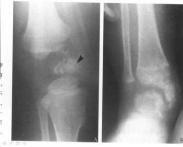

骨骺點狀發育不良又名康拉迪病(Conradi’s disease)、先天性點狀軟骨發育不良(chondrodystrophia congenita punletata)或點狀骨骺發育不良(dysplasia epiphysialis punctata)是由不同外顯率的常染色體隱性基因所引起的疾病。具有不相稱的短上臂和大腿,有短而粗的手指和足趾,關節強直,頸短,鼻梁扁平,上腭高,呈拱形。有些患者尚伴有先天性白內障,骨骺或心血管系統的缺陷。